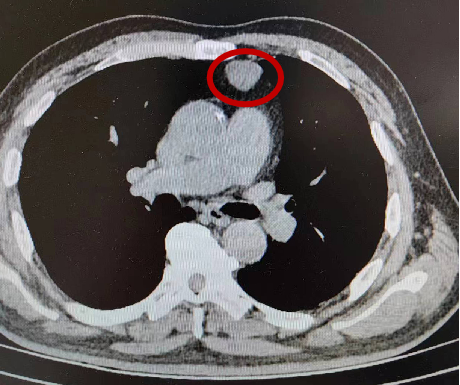

标志处为纵隔占位

既往,胸腺瘤基本都需要切开胸骨完成手术切除,但这种手术方式创伤太大,恢复时间很长。经过胸外专科的评估,认为患者肿块周围重要的血管、脏器未受到侵犯,于是选用了微创手术——胸腔镜人工气胸下全胸腺切除术,完整地切除了肿瘤和胸腺。